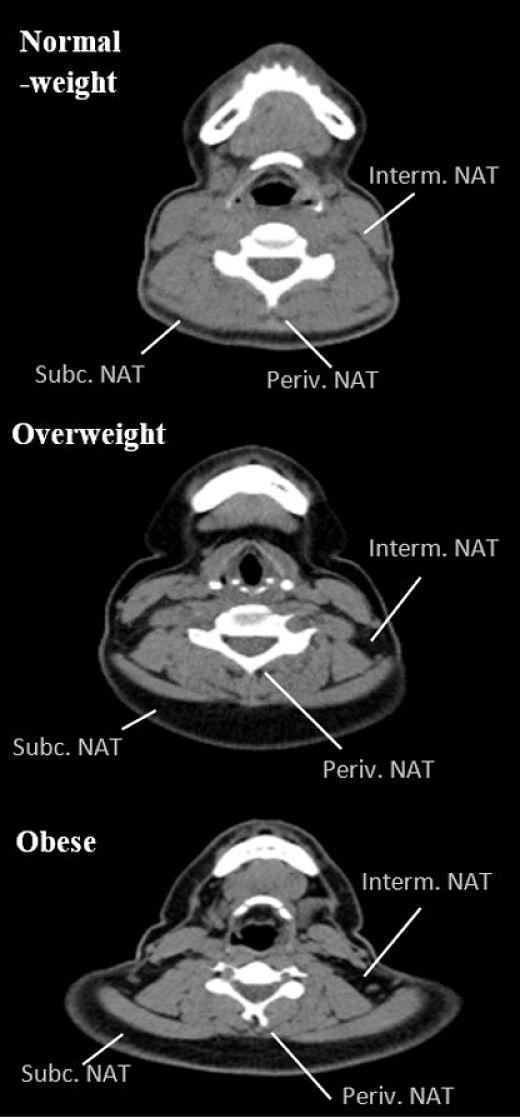

“Curiosamente, varios estudios han mostrado que la acumulación de grasa en el cuello (tanto depósitos superficiales como la papada como los depósitos más profundos, situados entre músculos y alrededor de las vértebras cervicales) aumenta de forma directamente proporcional al peso o adiposidad del sujeto, siguiendo patrones específicos de acumulación, según el sexo – explica la investigadora de la UGR María José Arias Téllez, una de las autores principales de este trabajo-. De hecho, el incremento de la acumulación de grasa en ciertos compartimientos/depósitos del cuello (principalmente profundos) está relacionado con la propensión a tener un mayor riesgo cardiometabólico. Sin embargo, la evidencia acumulada hasta el momento se basa en experimentos realizados en pacientes con tumores benignos/malignos u otras patologías crónicas, y si puede generalizarse a adultos relativamente sanos está aún por determinarse”.

La investigación muestra que la acumulación de grasa en el cuello medida con tomografía computada, así como su distribución en diferentes compartimentos,se asocia con mayor adiposidad total y central, mayor riesgo cardiometabólico y un estatus más pro-inflamatorio en adultos jóvenes sanos, de forma independiente a la cantidad de grasa total y visceral. Además, entre los hallazgos más relevantes, se observó que esta acumulación de grasa en el cuello era un factor tan potente (en términos de dirección y magnitud) como la acumulación de grasa visceral en la predicción del riesgo cardiometabólico y estado inflamatorio, especialmente en hombres.